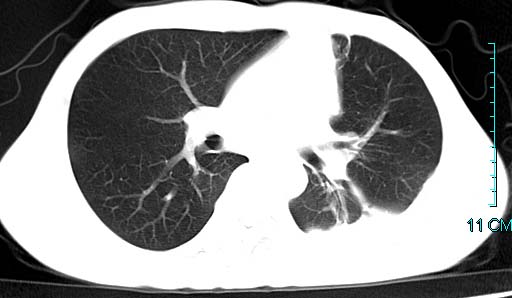

以下是引用qian在2006-3-28 14:32:00的发言:[br]左肺下叶大片状阴影,密度不均,见有条片影和空洞及气液平,少量胸腔积液伴有胸膜增厚,从图像看积液密度比水的密度高,结合病史,考虑左下肺化脓性炎症伴有脓胸。

以下是引用wawaquan在2006-3-28 22:25:00的发言:[br]左上肺舌段多发斑片影。结合“男24y咳嗽咳痰气促伴高热(38.5--39.5)20多天”及穿刺史,[br]考虑1 左下肺化脓性炎症;2脓胸。

以下是引用乡医在2006-3-28 18:37:00的发言:[br]左侧多发液气平面结合患者男24y咳嗽咳痰气促伴高热(38.5--39.5)20多天,查胸水:ldh239.3,总蛋白59.19,tb-ab阴性,利凡它试验+,红c2.7*109,白c1.08*109,分类淋巴92%分叶8%,考虑1脓胸2肺隔离征感染